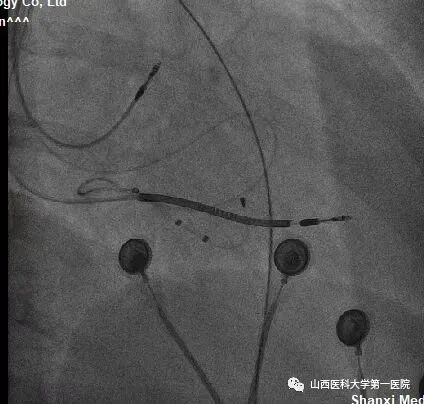

该患者为老年女性,主因反复间断胸闷10余年,加重1周入院。完善相关检查后提示:窦性心律,QRS波宽度187ms、完全左束支传导阻滞形态;心脏彩超显示:左室射血分数:25%,  左室舒末内径:72mm,符合ESC2021CRT指南I类适应证。术中,冠状窦静脉造影发现左室电极靶静脉(左室侧静脉)迂曲,双导丝导丝(Runthrough NS和Pilot50)均无法通过,采用逆向导丝技术,从后静脉逆向进入迂曲的静脉分支及侧支,成功进入左室侧静脉。

该患者冠状窦静脉侧支迂曲严重,前向无法进入左室侧静脉;同时,后静脉逆进入左室侧静脉的分支也非常迂曲,并且多处位置有膈神经刺激,左室电极多次调整,进入不同分支,并调整深度,最终寻找到起搏阈值好且无膈神经刺激位点。赵志强主任医师团队创造性的把冠脉PCI技术应用到手术中,并克服诸多困难,成功完成CRTD植入,期待患者后期心衰症状改善。